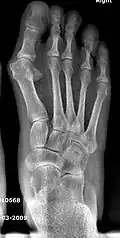

- For recurrence correction after osteotomy procedure (Fig. 8)

Late deformity recurrence can happen after osteotomy (bone-breaking) procedures because osteotomy surgeries do not specifically stabilize first metatarsal bone.

![]() Fig. 8a. Painful hallux valgus and metatarsus primus varus deformity recurrence of left foot after osteotomy surgery | |